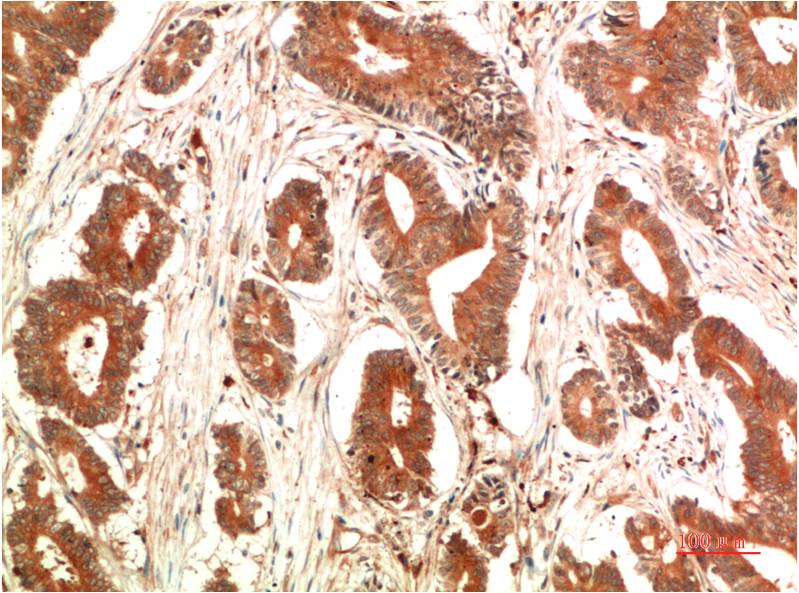

c-Jun Mouse Monoclonal Antibody(4G10)

Applications :IHC

| Recommended dilutions: | IHC 1:100-200 |

| Specificity: | The c-Jun Mouse Monoclonal Antibody can detects endogenous c-Jun proteins. |